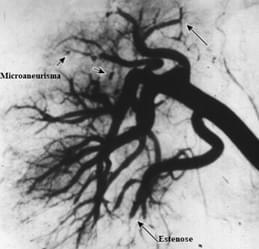

Quais os vasos acometidos na poliarterite nodosa?

Médios (principalmente) e pequenos vasos